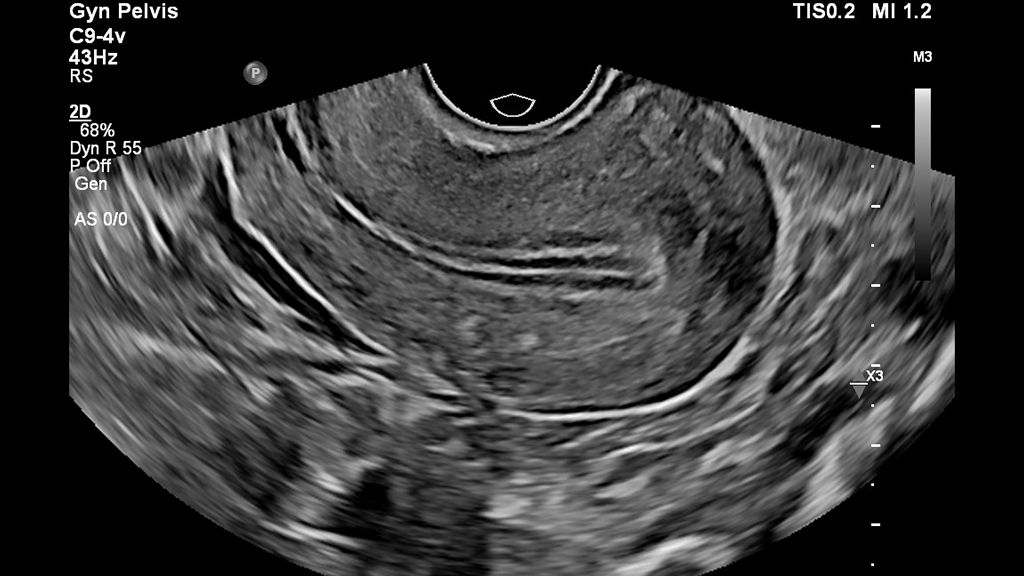

• Image of pelvis using C9-4v transducer

Sagittal image of the uterus